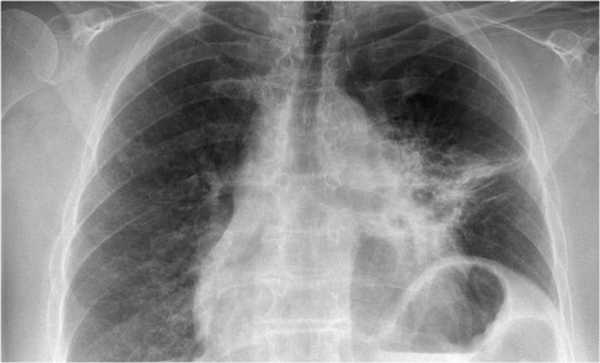

Во многих случаях ателектаз является первым признаком рака легких, поэтому очень важно выявить специфичные для ателектаза и дисектаза изменения.

Ключевые изменения на рентгенограмме представлены ниже:

- Уменьшение легкого в объеме, как следствие подъем купола диафрагмы, смещение средостения в патологическую сторону, смещение горизонтальной и косой междолевой щели.

- Безвоздушный участок легкого с отсутствием вентиляции.

Ниже представлен снимок пациента с туберкулезом, на котором визуализируется ателектаз верхней доли правого легкого, а также обратите внимание на девиацию трахеи.